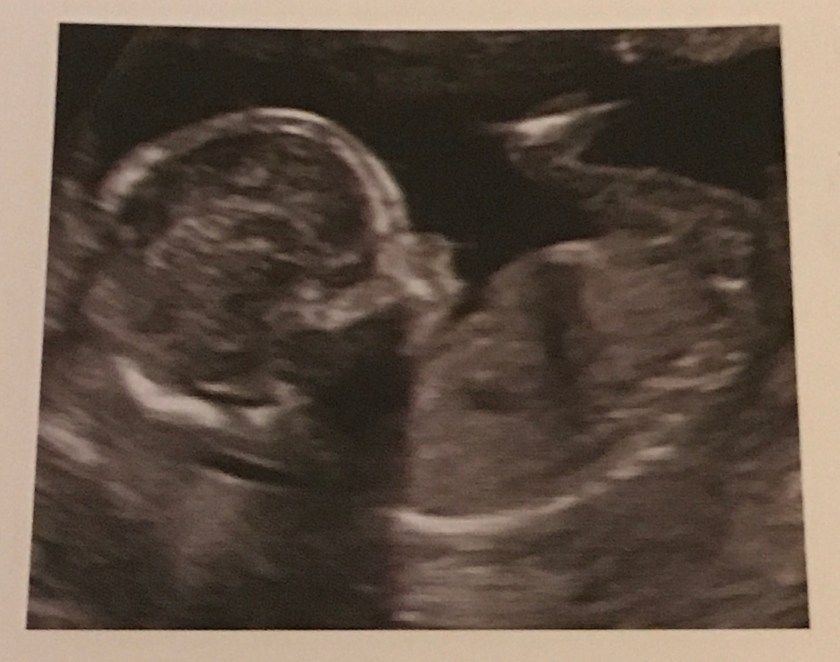

This example ultrasound shows what baby would appear like. Dr. G suggested he might only do a heart reading the next visit on Friday and not an ultrasound, so I probably will not have new pictures to share.